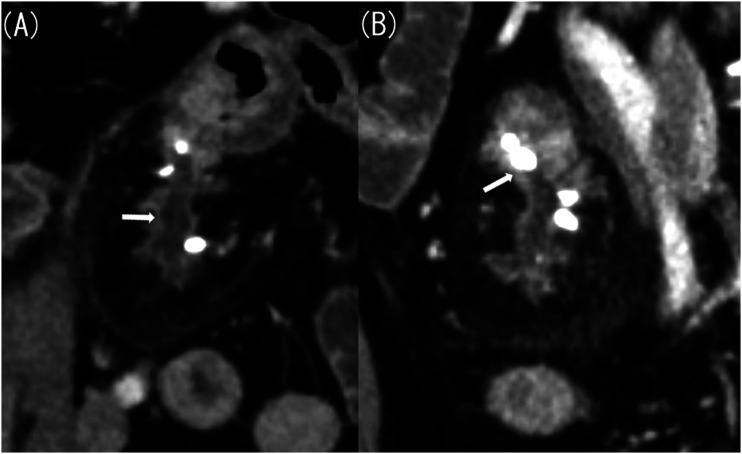

Ectopic pancreas within the mesentery is rare. In this case report, a 61-year-old man with an ectopic pancreas within the jejunal mesentery for over 20 years developed chronic pancreatitis that progressed to acute exacerbation. Our computed tomography (CT) performed for acute abdomen assessment suggested acute appendicitis or Meckel's diverticulitis. However, a CT scan taken 20 years ago revealed a structure indicative of an ectopic pancreas in the mesentery, and further imaging findings taken 10 and 4 years ago confirmed progression to chronic pancreatitis. Furthermore, we found a pancreatic stone confined in the luminal structure that corresponded to the main pancreatic duct; this stone eventually caused acute exacerbation. In summary, we report a case of mesenteric ectopic pancreas that showed typical findings of progression and acute exacerbation of chronic pancreatitis on CT.